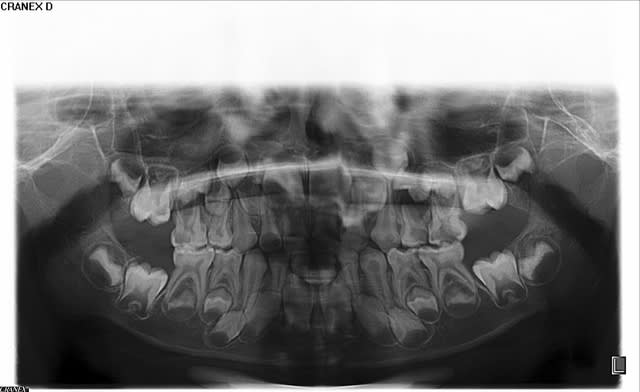

J'ai un jeune " con" à qui j'ai fais une endo sur 47, qui n'ayant plus mal, a raté son rendez vous et m'a tel 2 jours aprés, non pour s'excuser mais dire qu'il avait une douleur terrible, insupportable.....à venir de suite......

Il revient à son rendez vous et me dit que sa 47 le lance, Z6 endo ok.

Dialogue de sourds......c'est celle la ...etc.

Je prends un tube de free.. vaporise sur un coton, lui dit de lever la main si il sent.

47 ......rien

46, 45 il lève timidement la main

48 ......... la jouissance.

Je lui ai dit "Qui a raison ?"

"OUI OUI"

Je lui ai dit la prochaine fois endo de la 48 et sois à l'heure.